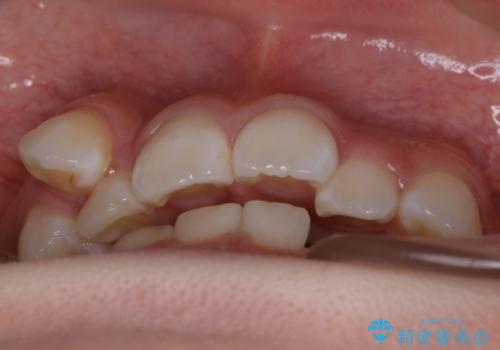

- 歯のガタつきを主訴にご来院されました。

ガタつきがあるだけでなく、元々永久歯が欠損している「先天欠如」で歯の本数が少なく噛み合わせ等も治療する必要がありました。

かなり特殊な状況からの矯正治療になるため抜歯する本数や位置、並んだあとのスペースのコントロールを慎重に計画し、マウスピース装置のインビザラインで治療を開始しました。